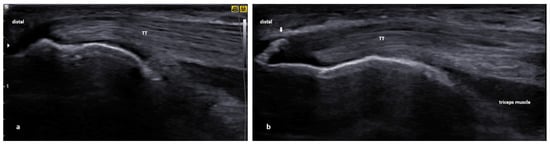

3.4. Distal Triceps Tendinopathy

3.4.1. Essential Anatomy

3.4.2. US Scanning and Guided Injection